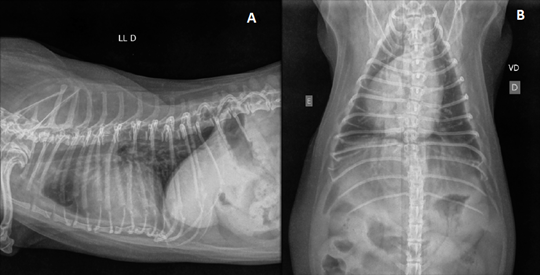

Arterial blood gases showed severe hypoxemia with hypocapnia, and the female dog was kept in oxygen therapy in an incubator with an inspired oxygen concentration between 40 and 50%. An venous access was fixed in the right forelimb and Ringer's lactate fluid therapy was started at a rate of 2ml/kg/h and KCl replacement was maintained. Intravenous furosemide 2mg/kg was administered. In the chest X-ray was observed an overall increase in the cardiac silhouette with dorsal displacement of trachea (Figure 1).

Figure 1 Right lateral (A) and dorsoventral (B) chest radiography. Radiography pictures demonstrating global enlargement of the cardiac silhouette, dorsal displacement of the thoracic tracheal path and caudal main bronchi.

The electrocardiogram did not show major alterations suggestive of pulmonary hypertension, as did the chest X-ray, which showed an overall increase in the size of the heart. The electrocardiographic or radiographic changes alone not provide the diagnosis of pulmonary hypertension.1,6